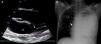

Catheter placement in the cavoatrial junction. (A) Modified parasternal long-axis view of the superior vena cava. The catheter is seen in the top of the right atrium (RA) at the cavoatrial junction. To obtain the modified parasternal view, starting from the standard parasternal view, the transducer is placed parallel to the sternum and tilted to the right side of the patient until the superior vena cava is visualised. (B) Plain X-ray of the same patient showing correct placement of the catheter.

We used this technique for 6 months to insert TIVADs. Cannulation was performed in the operating theatre by a paediatrician with experience in ultrasound-guided venous catheter insertion and a paediatric surgeon. A 12MHz linear probe was used to obtain a long-axis view of the BCV (left and right) from the supraclavicular fossa. A 21G needle was inserted at the confluence of the right subclavian vein and the BCV. The BCV was selected in every case so that the transducer could be placed on the left side of the patient, away from the surgical field. After advancing the guidewire, it was replaced by a peel-away introducer. A 6.5F catheter was inserted through the introducer in the right atrium with echocardiographic visualisation through the subcostal window with a 2–4MHz cardiac probe. Once the catheter tip could be visualised in the right atrium, it was pulled back to the cavoatrial junction. Correct placement of the catheter in the superior vena cava was confirmed in the modified parasternal long axis view (Fig. 1). At this point, the surgeon made the subcutaneous tunnel and fitted the port, after which the procedure was completed with the customary technique. Four procedures were performed in 2 boys (aged 5 and 10 years) and 2 girls (aged 11 and 15 years) with body weights ranging between 16 and 46kg. The indications for TIVAD placement were lymphoma in 3 patients and neurodegenerative disease in 1. Catheter insertion in the BCA was successful in the first puncture and the catheter was placed correctly and without associated complications in every case. The TIVADs continued to work correctly after a median followup of 9 months (interquartile range, 6–11 months).